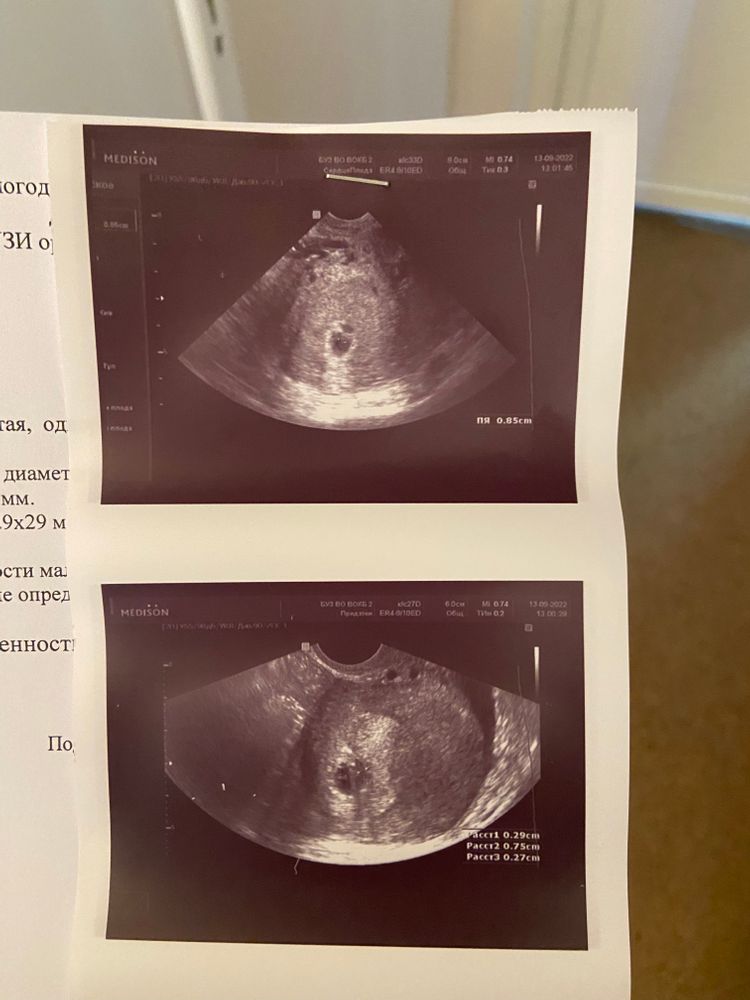

Всем привет. Лежу в больнице с ковидом, здесь же сильно заболела поясница.. Проверили по узи - гематома 29х29 мм. Срок примерно 5+4 недели.

Во-первых, из-за ковида одна узист сказала, что на таком сроке высокий риск развития патологий, даже сказала, что прервала бы беременность на моем месте.. И вторая обнаружила вот такую гематому. Выделений никаких нет.